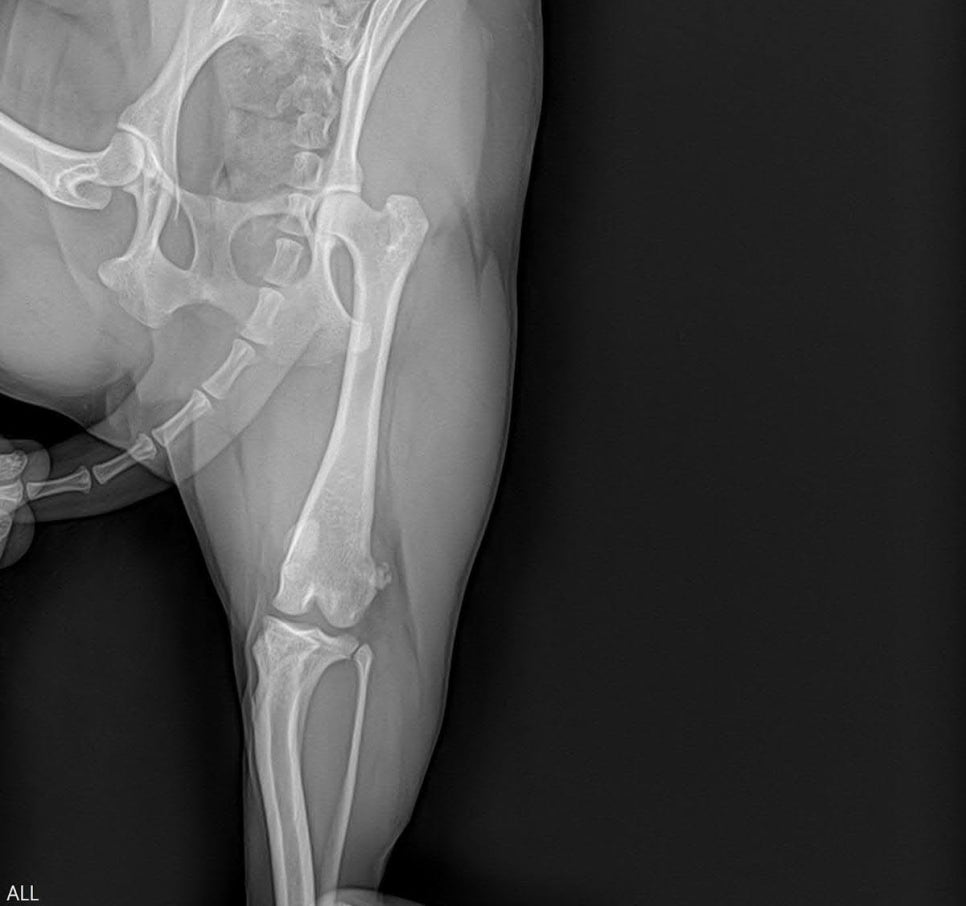

강아지 슬개골탈구 좌측 교정 수술 케이스

7살, 5.9kg의 중성화 수컷 비숑 환자 B는 이미 한 차례 본원에서 정형외과 수술을 받았던 환자입니다. 작년 8월, 우측 슬개골탈구와 십자인대 단열이 동시에 확인되어 교정 수술을 진행했으며, 이후 재활 과정을 거쳐 안정적으로 회복했습니다.

하지만 최근 들어 좌측 뒷다리에서 간헐적인 불편감이 관찰되었고, 체중을 완전히 싣지 못하는 모습이 점차 잦아졌습니다. 보호자님께서 이상을 인지하고 재내원하셨습니다.​

정형외과 평가 및 진단

내원 당시 보행 분석과 무릎 촉진 검사를 시행했습니다. 우측은 수술 부위가 안정적으로 유지되고 있었으며, 관절 정렬과 기능 모두 양호한 상태였습니다.

​반면 좌측 슬관절에서는 슬개골 탈구가 반복적으로 확인되었고, 이전보다 탈구 정도가 진행된 양상이 관찰되었습니다. 방사선 촬영을 통해 구조적 변화를 확인한 결과, 좌측 슬개골탈구가 명확히 진단되었습니다.

​B는 과거 우측 수술 후 좋은 회복 경과를 보였지만, 반대편 무릎은 시간이 지나면서 점진적으로 악화된 사례였습니다.

​슬개골탈구는 양측성으로 나타나는 경우가 많아, 한쪽 수술 이후에도 반대편 진행 여부를 지속적으로 관찰하는 것이 중요합니다.현재 단계에서는 수술적 교정이 필요하다고 판단하였고 보호자님과 현재 진행 정도, 수술 방법, 회복 과정에 대해 충분히 상의한 뒤좌측 슬개골 교정 수술을 결정했습니다.

마취 전 혈액검사 및 방사선 검사를 통해 전신 상태와 수술 적합 여부를 확인했고 특이 이상 없이 안정적인 상태로 확인되었습니다.

수술 전 흉부방사선 검사 / 출처: 라온동물메디컬센터